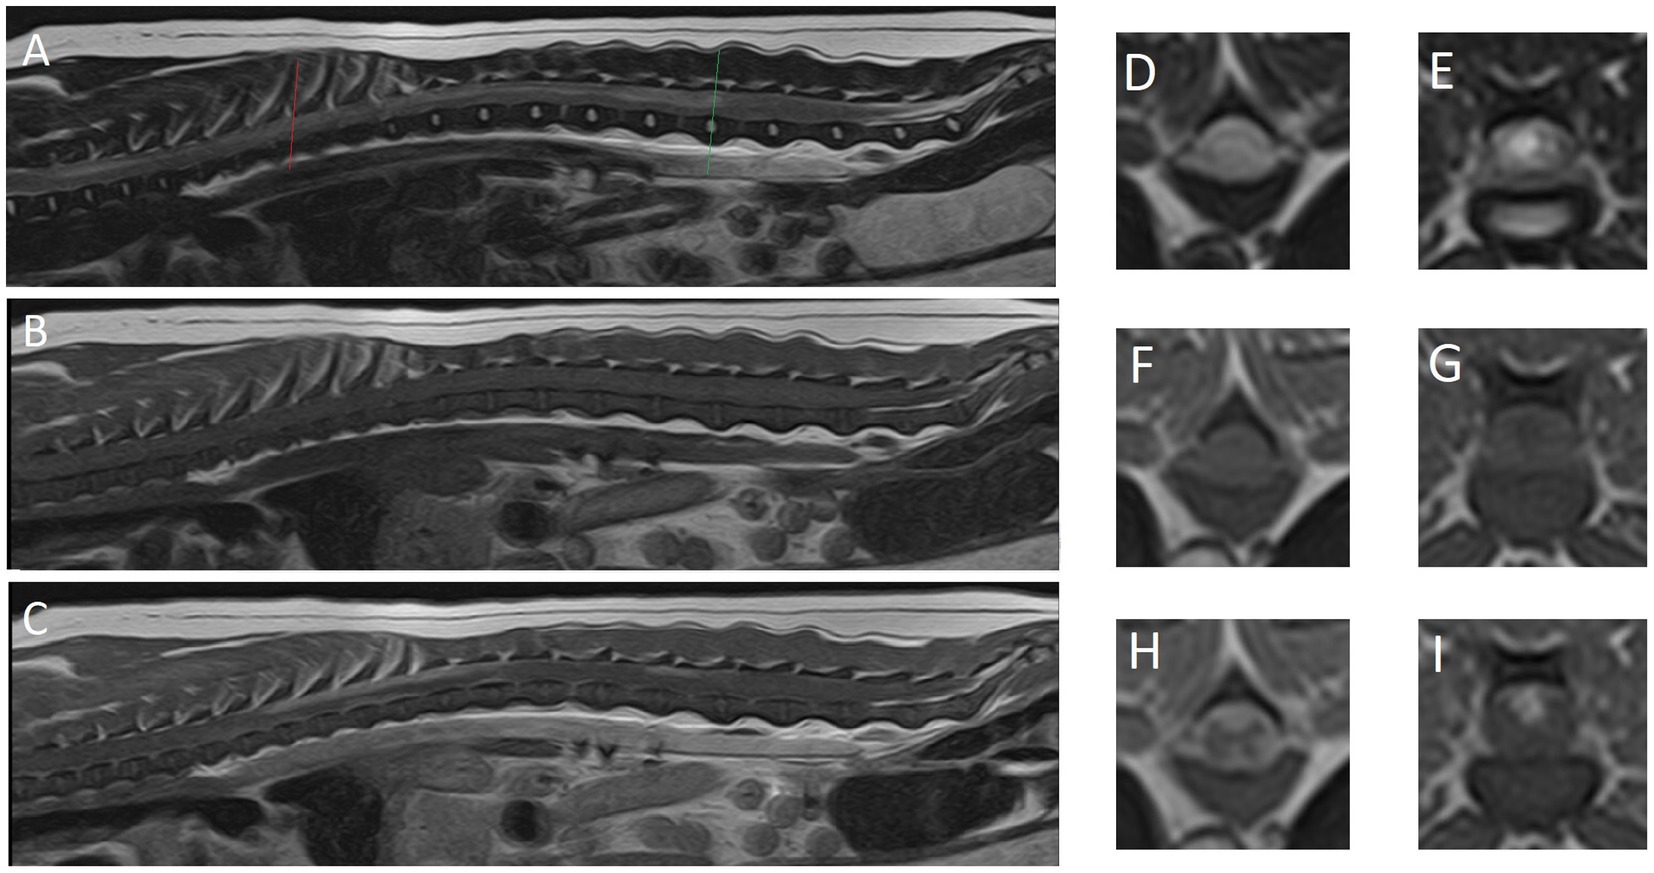

Se realizó un estudio de resonancia magnética de alto campo (RM; 1,5 T Canon Vantage Elan) de la médula espinal toracolumbar desde el nivel de la 1ª vértebra torácica hasta el sacro bajo anestesia general. La premedicación incluyó 0,4 mg/kg de metadona y 6 μg/kg de dexmedetomidina, seguidos de 3 mg/kg de propofol en bolos para la inducción de la anestesia. Se utilizó isoflurano al 2-3% para el mantenimiento del plano anestésico. Las secuencias realizadas incluyeron: sagital ponderada en T2 (T2W), recuperación sagital de la inversión tau corta (STIR), T1W sagital, STIR dorsal, T2W transversal, T1W transversal, T2* transversal, T1W post-contraste transversal, T1W post-contraste sagital 3D y T1W post-contraste transversal con saturación de grasa. Las imágenes de RM no revelaron signos de enfermedad del disco intervertebral, la señal del núcleo pulposo de todos los discos intervertebrales fotografiados era T2 hiperintensa. Se observó una lesión intramedular irregular y mal definida, de extensión variable, pero observada desde T1 hasta L4 (Figura 1). Tanto la materia gris como la blanca se vieron afectadas. Toda el área de la sección transversal del cordón se vio afectada a nivel de T9. La lesión era heterogénea, de moderada a marcada T2W hiperintensa en comparación con el resto de la médula y T1W isointensa. El parénquima de la médula espinal mostró un realce moderado y parcheado del contraste de T7 a T12 y de L1 a L3. El cordón parecía hinchado a esos niveles y las meninges circundantes estaban engrosadas y aumentaban el contraste, incluido el realce a lo largo de la fisura medial ventral a nivel de T9. Una punción lumbar de LCR no tuvo éxito.

Figura 1. Imágenes de resonancia magnética del caso reportado. (A) El plano sagital medio, (D) el plano transversal y (E) el plano transversal son imágenes ponderadas en T2. (B) El plano sagital medio, (F) el plano transversal y (G) el plano transversal son imágenes ponderadas en T1. (C) El plano sagital medio, (H) el plano transversal y (I) el plano transversal son imágenes post-contraste ponderadas en T1. (D, F, H) El nivel de T8 (línea roja). (E, G, I) El nivel del disco intervertebral L3-4 (línea verde).

En segundo lugar, el valor y las limitaciones de la RM para diagnosticar o excluir los diferenciales de la lista de diagnóstico diferencial se reflejan en este informe de caso. Los hallazgos de la resonancia magnética, aunque muy sugerentes, no confirmaron un proceso inflamatorio. No se identificó IVDD en las imágenes y posteriormente se excluyó de la lista de diagnóstico diferencial. Dado que la punción del LCR falló, no se dispuso de más indicaciones clínicas para corroborar la sospecha de inflamación o posiblemente identificar células neoplásicas. La histopatología post-mortem confirmó las sospechas de inflamación, pero también nos brindó la oportunidad de evaluar las similitudes entre los hallazgos diagnósticos por imagen (Figura 1) con los hallazgos histopatológicos (Figura 2). Nos gustaría que el lector los comparara entre sí y apreciara la forma en que los hallazgos de la RM reflejan en gran medida los hallazgos histológicos, pero también apreciamos que los hallazgos histopatológicos son aún más extensos de lo que se puede ver en las imágenes de RM.

Los hallazgos de la resonancia magnética en nuestro caso consistieron en un área extensa de lesiones hiperintensas T2W multifocales (probablemente confluentes) que eran isointensas T1W y mostraban realce del contraste parenquimatoso (médula espinal) y meníngeo. Se han descrito características de meningomielitis de origen desconocido en perros por resonancia magnética (18). Estos incluyen: focales (71%), multifocales (19%) o sin lesiones (10%); lesiones intramedulares hiperintensas mal definidas en las imágenes de T2W que son isointensas en las imágenes de T1W; realce del contraste parenquimatoso (86%); y realce del contraste meníngeo (81%). El realce del contraste meníngeo podría ser el único hallazgo (18). En la resonancia magnética se pueden identificar lesiones cerebrales concurrentes, lo que sugeriría meningoencefalomielitis que puede confirmarse mediante un examen histológico (18). El extenso realce del contraste parenquimatoso y meníngeo observado en los estudios post-contraste realizados en nuestro caso proporciona información valiosa para dar preferencia al diagnóstico de meningomielitis.